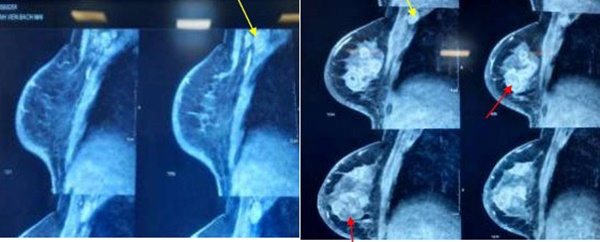

Hình ảnh cộng hưởng từ vú cho thấy tổn thương u vú đa ổ (mũi tên màu đỏ). Hạch nách phải (mũi tên màu vàng). Ảnh: BVCC

Do bệnh nhân không được tiếp cận và điều trị ở ngay thời điểm này. Bệnh nhân đến viện khi đã xuất hiện ung thư vú thể viêm đa ổ, di căn hạch nách, chưa di căn xa.